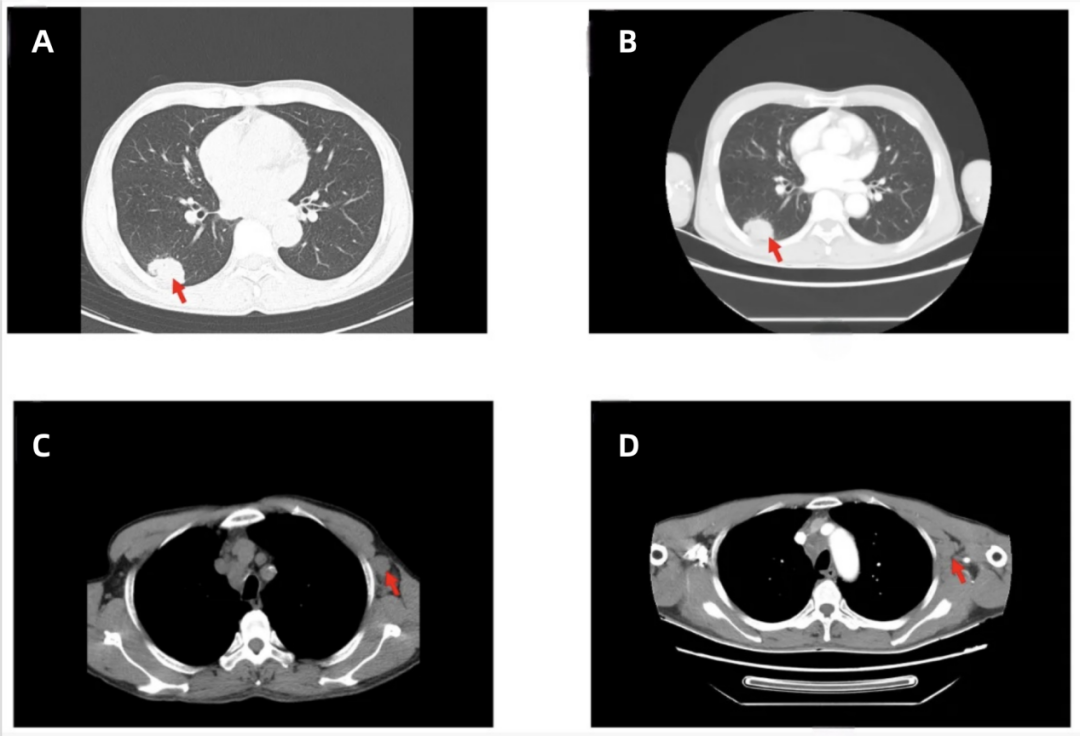

患者无明显诱因出现咳嗽、咳痰,伴胸闷不适,于2025年6月1日在当地医院就诊,胸部CT提示“右肺下叶占位性病变(约3.7×2.5cm)(图1A),伴左腋窝淋巴结肿大(图1C)”。当地医院按“肺部感染”予布地奈德

颈部、胸部、腹部增强CT:右肺下叶占位,大小约36mm×23mm(图1B);伴左侧腋窝淋巴结肿大(图1D)。

图1 初诊时右肺病灶和左侧腋窝淋巴结(红色箭头指向病灶)[1]